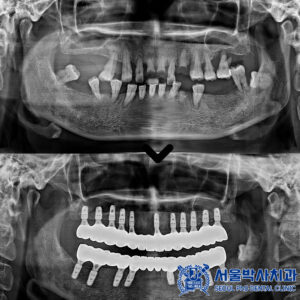

산성동치과 잇몸이 붓고 이가 시려요. MTA 신경치료와 어금니 크라운으로 자연치아 살린 사례   안녕하세요. 산성동치과 서울박사치과입니다.   치아는 겉으로 보기에 문제가 없어 보여도, 안쪽에서는 시간이 지나며 변화가 생길 수 있습니다.   특히 오래 전에 크라운 치료를 받은 치아는 외부 자극으로부터 보호되고 있어 통증이나 이상을 느끼기 어려운 경우가 많습니다.   하지만 더보기…